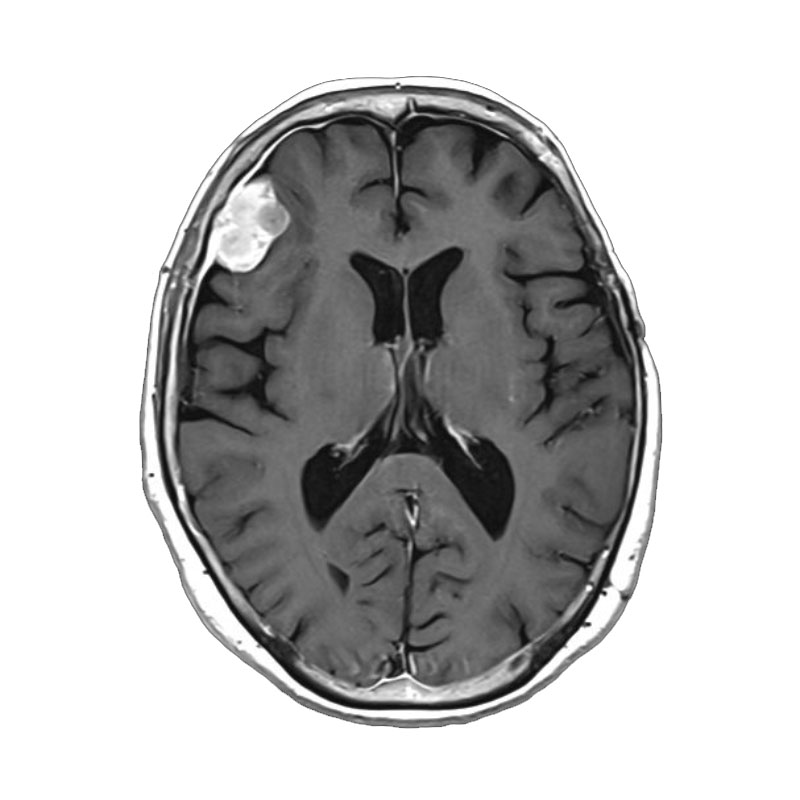

脳動静脈奇形

摘出術

南田/野本/古谷/元永